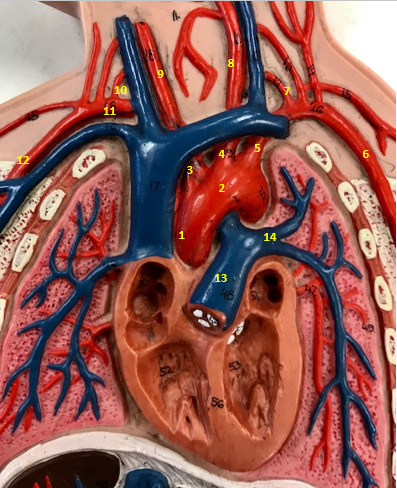

Aorta

Name #2

Brings blood out of left ventricle

Function of aorta

Brachiocephalic artery

Name #3

Supplies oxygenated blood to right arm shoulder neck and head

Function of brachiocephalic artery

Left common carotid artery

Name #4

Supplies oxygenated blood to left neck and head

Function of left common carotid artery

Left subclavian artery

Name #5

Supplies oxygenated blood to left arm shoulder

Function of left subclavian artery

Left axillery artery

Name #6

supplies blood to left armpit and upper limb

Function left axillary artery (6)

Left vertebral artery

Name #7

Supplies blood to brain and spinal cord

Function of left vertebral artery (7)

Left common carotid artery

Name #8

Supplies blood to left neck and head

Function of left common carotid artery (8)

Right common carotid artery

Name #9

Supplies oxygenated blood to right neck and head

Function of right common carotid artery (9)

Right vertebral artery

Name #10

Supplies blood to brain and spinal cord

Function of right vertebral artery (10)

Right subclavian artery

Name #11

Supplies blood to right arm and shoulder

Function of right subclavian artery

Right axillery artery

Name #12

Supplies blood to right armpit and upper limb

Function of right axillery artery (12)

Pulmonary trunk

Name #13

Bring blood out of right ventricle to lungs

Function of pulmonary trunk (13)

Left pulmonary artery

Name #14

Bring blood to left lung

Function of left pulmonary artery (14)